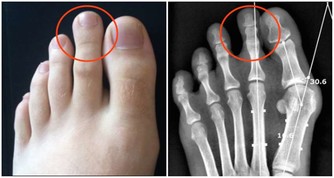

心臟不好,這地方要常按!每天按一次,勝吃救心丸 2016-06-14 10:38 健康人的手掌可以用四個字概括,就是紅潤光澤,反之,就預示著身體不舒服,甚至有疾病。

心臟的手診部位在手掌大魚際處,以大拇指平分線順直沿線為界(如圖),左側代表左心,右側代表右心;上2/5為心房,下3/5為心室。這就是心區的位置。 心臟好不好,看這個位置就知道!在這個位置的「大魚際」,是隨身攜帶的救心丸,每天按一下,緩解心臟壓力,保護心臟有奇效!

心病,多在大魚際上有反映! 魚際,簡單理解就是魚腹。攤開手掌,在手掌心靠近大拇指的地方,皮膚顏色泛白,肌肉隆起,叫大魚際。 心病,一般多在大魚際上有反映,下面三種症狀,一定要特別注意,對於緩解心病、防治心臟疾病非常重要!

1有紅色斑點、血絲:心火旺! 如果在心區位置發現紅色的斑點,或者有血絲但尚未抱團,說明最近心火比較盛,容易有心煩的症狀。 中國中醫科學院民間傳統醫藥研究室主任劉劍鋒表示,心病還需心藥醫,同時,也可以通過手療來緩解症狀。 方法: 用左手按壓右手心區有紅點的位置,尋找有明顯酸痛感的點,按住不動,待酸脹感產生再向指尖方向推,反覆推揉幾分鐘。按摩完右手後,再用同樣的方法按摩左手。

2大魚際「長斑」,警惕心梗! 如果左右手大魚際同時出現暗紅色斑點,說明心肌正在缺血,雖然尚未發作,卻有發生心肌梗死的可能,是一種更危險的信號。 建議這類人儘快到醫院進行檢查,以免延誤病情。此外,生活中應使體力和精神充分休息,減少心肌的工作,飲食以易消化、低鹽、低熱量為主,保持大便通暢。

3大魚際有血絲團,警惕心絞痛! 如果左手和右手的大魚際處同時出現紅色血絲團,就說明心臟有缺血症狀,有引發心絞痛的可能。 發現血絲團一定要當回事兒,除經常按揉局部血絲團並向指尖方向推搓外,還要儘快到醫院檢查、治療。

按揉大魚際,勝吃救心丸 中醫認為,心區分布在手掌的大魚際處,通過該區發紫、血絲等表現,可以反映心煩、心慌、冠心病等病症。 而通過大魚際來養心、護心,預防心臟病,是個很不錯的日常保健方法,這也是心臟不好的人,每天必做的安心之法。 按揉方法: 用右手按揉左手的大魚際,先順時針緩慢、用力地按揉36圈,做完後再用同樣的方法逆時針按揉36圈,右手做完換左手做。每天有空的時候就按揉一下。